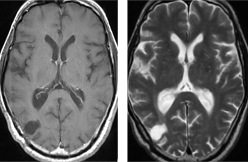

卵巣癌による右前頭葉を中心に多発転移性脳腫瘍に対して放射線治療単独(全脳照射)のみで腫瘍が著明に縮小しました。その後再発なく経過しています。

一般的に腫瘍サイズが小さい場合(2~3cm以下)は放射線治療が優先されます。最近では全脳照射後の認知症状を回避するべく、ガンマナイフが選択されるようになってきています。